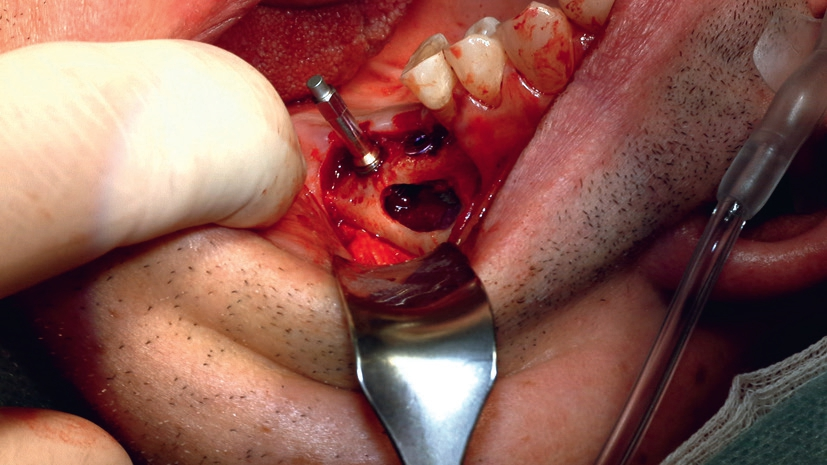

Im vorliegenden Fall kamen die Piezochirurgie und die Bestimmung des Resonanz-Frequenz-Analyse-Wertes (RFA) zum Einsatz, um Knochenaufbau und Implantation in nur einer Sitzung durchzuführen, ohne die Stabilität des Zahnersatzes zu gefährden (Abb. 2).

Knochensparende Piezochirurgie

Bei dem behandelten Patienten wurde die Schneider-Membran angehoben, um das Knochenaugmentat zwischen dem respiratorischen Epithel der Kieferhöhle und dem Kieferhöhlenboden einzubringen. Hierbei wurde ein Gemisch aus autologem Eigenknochen und xenogenem Knochenersatzmaterial unterhalb der elevierten Kieferhöhlenmembran eingebracht und mit einer resorbierbaren Membran verschlossen, um ein gesteuertes Knochenwachstum (GBR) im augmentierten Bereich zu gewährleisten. Dieser Eingriff erfolgte im Rahmen einer Implantatplanung mit 3D-Technologie, die besonders bei einem dünnen Kieferknochen wichtige Dienste bei der Bestimmung des Restknochenangebots leistet.